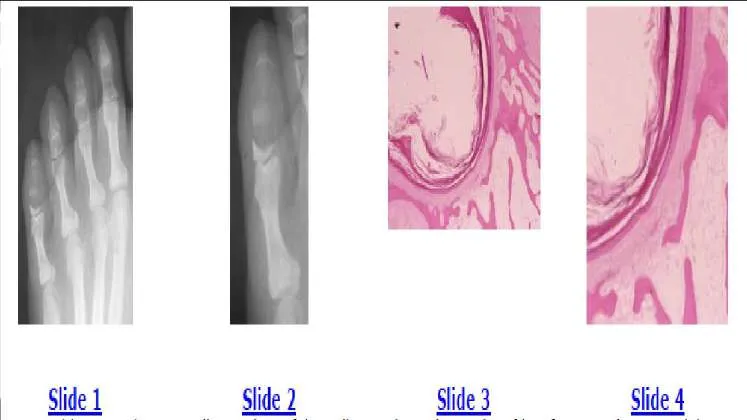

Slide 1 Slide 2 Slide 3 Slide 4 A 35-year-old woman has a swollen and painful small toe. The radiographs of her foot are shown in Slides 1 and 2, and biopsy specimens in Slides 3 and 4. The most likely diagnosis is:

The radiographs show an expansile, lytic destructive lesion, which has replaced the distal and middle phalanxes of the little toe. The biopsy specimen shows the squamous epithelium of the skin with keratin production extending into the medullary cavity of the bone. The patient has an epidermoid inclusion cyst. These cysts are usually secondary to trauma. The treatment should be curettage and grafting.C orrect Answer: Epidermoid inclusion cyst